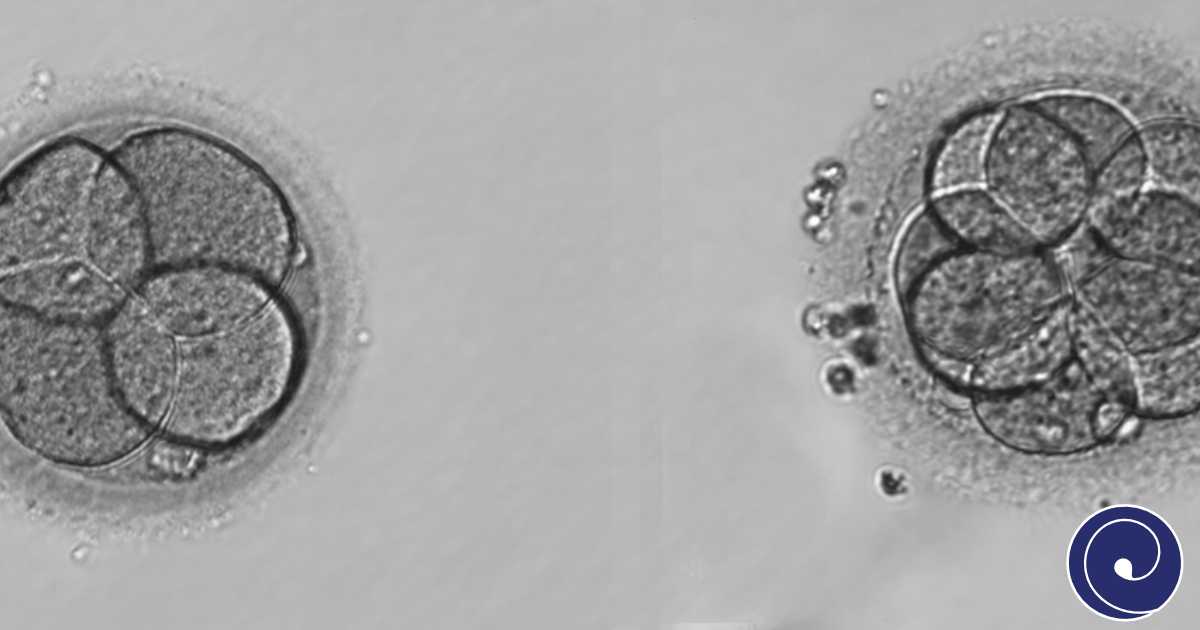

Praćenje razvoja embrija predstavlja jedan od najvažnijih koraka u procesu vantjelesnog oplodnja (IVF). Cilj ovog procesa je da se prati kvalitet i napredak embrija kako bi se odabrali oni sa najvećim potencijalom za uspješnu implantaciju i trudnoću.

Tradicionalno, razvoj embrija se prati kroz period od nekoliko dana u inkubatoru, pri čemu se embriji redovno vade iz inkubatora u laboratoriju radi vizuelne procene pod mikroskopom. Embriolozi prate ključne faze razvoja, kao što su:

Ovaj pristup omogućava osnovnu procjenu kvaliteta embrija, ali je ograničeno jer je praćenje moguće samo u određenim vremenskim intervalima. Često se praćenje vrši jednom ili dva puta dnevno.